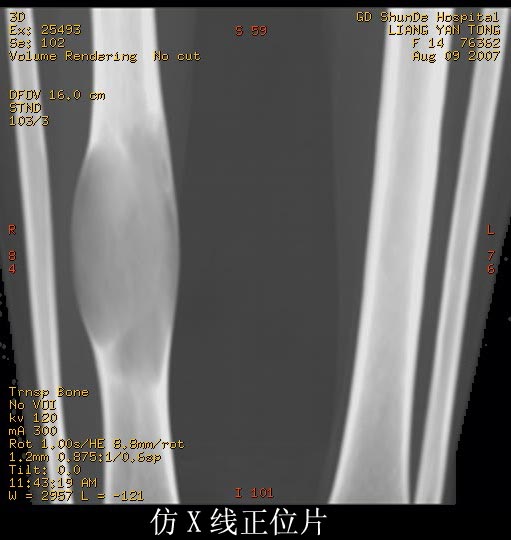

女性,14岁。自觉右胫骨下段前缘隆起。x线示:右胫骨干骨膨隆,骨皮质压迫性变薄。

支持:骨纤维异常增殖症可能。诊断依据有:1病灶呈囊状改变位于管状骨,边硬化不明显,内缘稍粗糙,囊内见条骨纹和斑点状致密影。2磨玻璃样改变,髓腔膨胀呈磨玻璃样密度。3丝瓜筋改变国缘锐利如虫蚀样,类似溶骨性转移的骨破坏。

考虑骨纤维异常增殖症。因为骨干呈囊状膨胀改变,骨皮质变薄,囊内散在条状骨纹。其内有斑点状致密影。为本病征像之一。

支持骨纤维异常增殖症。特点;膨胀性改变,呈毛玻璃样密度,其内有条点状影,没有硬化缘

没有死骨,没有骨膜反应,软组织没有肿块形成。

胫骨中段皮质内环绕并突入髓腔膨胀性生长的软组织密度病灶,内缘粗糙,外缘光滑无中断,病灶内可见小点状钙化.未见骨膜反应及瘤骨;软组织显示如常,未见肿块及异常密度.

考虑:胫骨中段良性肿瘤或肿瘤样病变,骨纤可能大.

右胫骨中段囊性、膨胀性改变,病变呈中心性,沿骨的纵轴生长,病变区骨皮质明显变薄,骨包壳完整,无中断,病变边缘无明显硬化,未见明显骨膜反应,周围软组织无肿胀。首先肯定的是骨良性病变(良性骨肿瘤或肿瘤样病变。有以下几种可能: